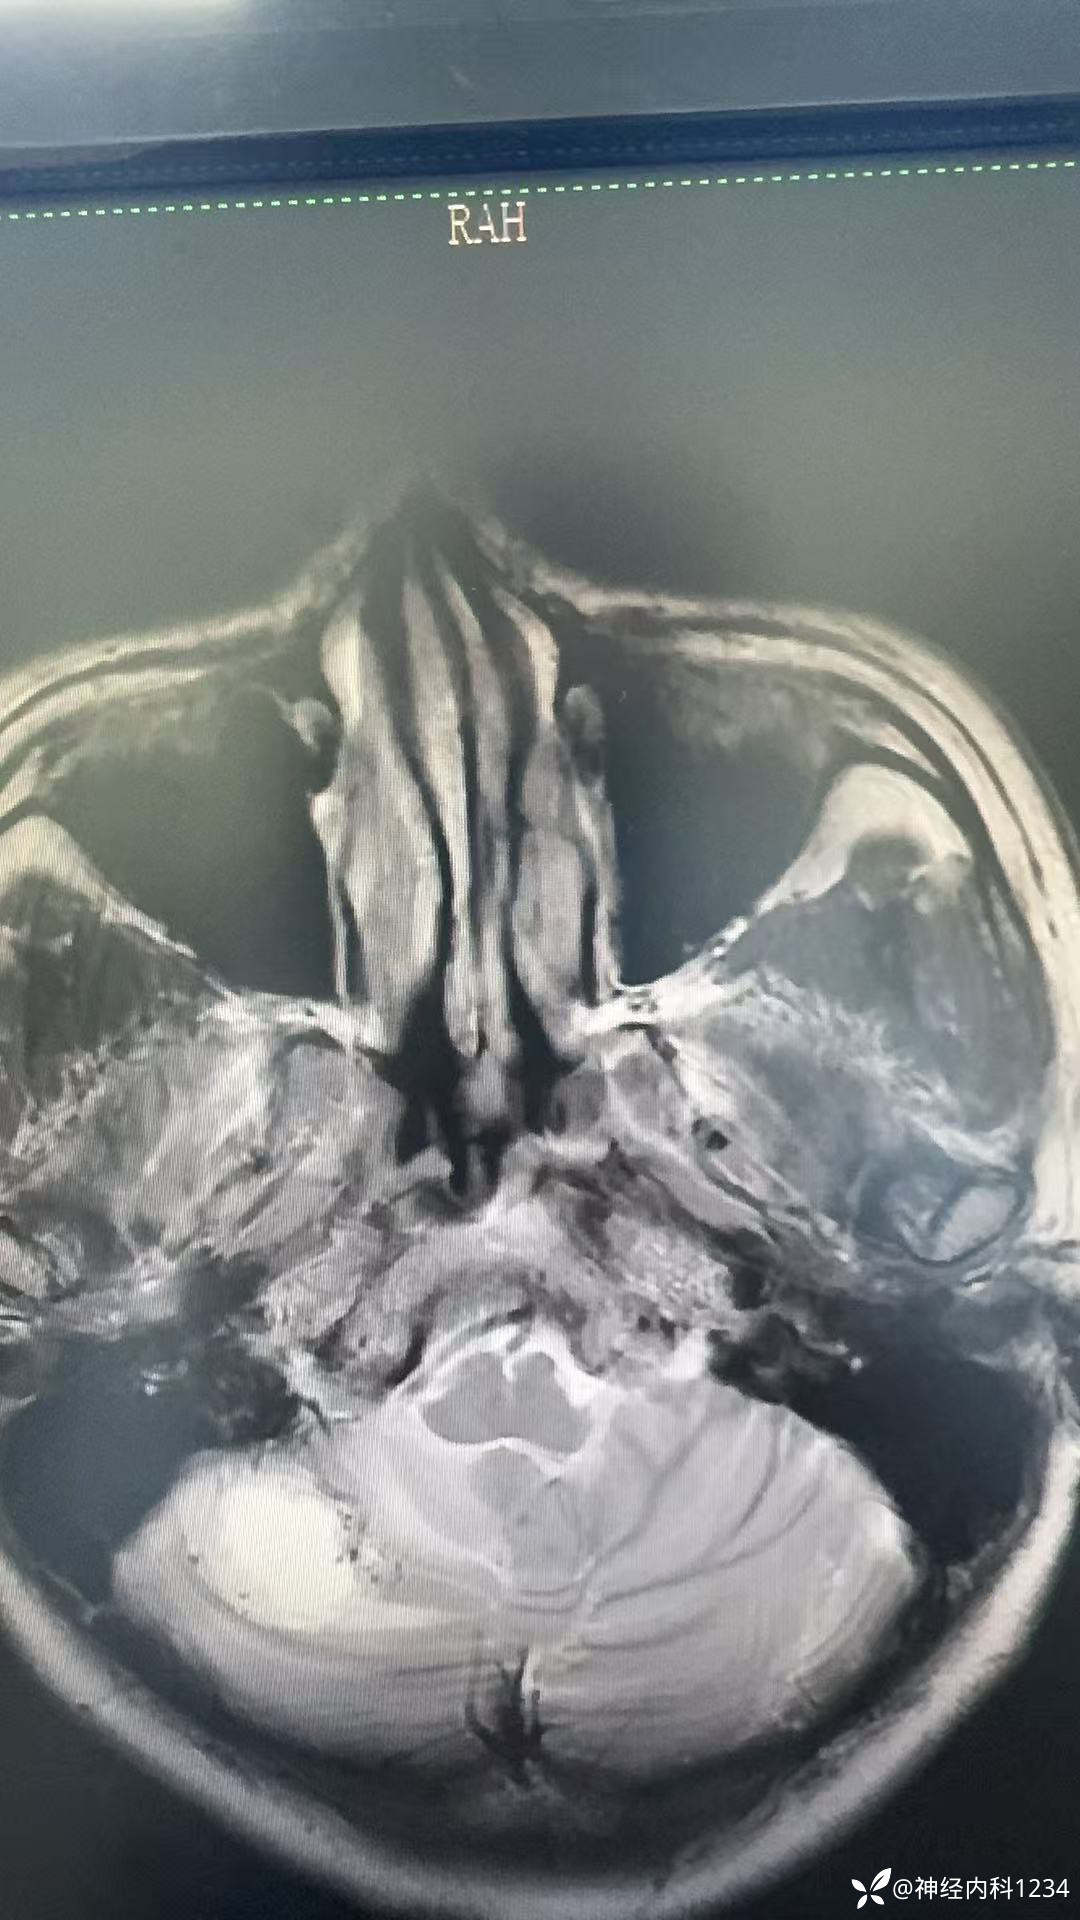

病例信息

病例讨论

考虑啥肿瘤